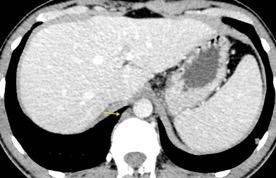

Nódulos pulmonares múltiples. (flechas verdes). Masas paratraqueales. (flechas amarillas). Dudoso ensanchamiento retrocrural (flechas negras). sigue….

Ttawfik A et al. Trans-diaphragmatic Pathologies: Anatomical Background and Spread of Disease on cross-sectional Imaging. Current Problems in Diagnostic Radiology. 2021.

T. mixto de células germinales del testículo

izquierdo Metástasis pulmonares. (flechas verdes). Ganglios paratraqueales. (flechas amarillas). Ganglios retroperitoneales (flechas negras)

Tawfik A et al. Trans-diaphragmatic Pathologies: Anatomical Background and Spread of Disease on cross-sectional Imaging. Current Problems in Diagnostic Radiology. 2021.